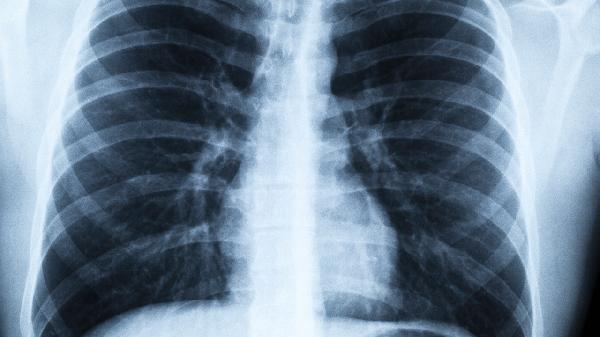

1、体检发现结节不必过度恐慌

90%以上的微小结节属于良性,遵医嘱定期复查即可。

2、这些症状要当心

如果伴随持续咳嗽、痰中带血、胸痛等症状,需要进一步检查。